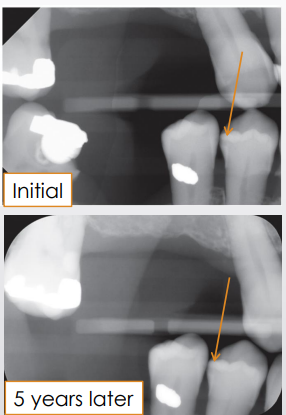

when decision is made to NOT manage the lesion surgically, what should be done to ensure proper monitoring of the lesion

follow-up period based on pts caries risk

new images should be as similar as possible for accurate comparison to see any progression

how can depth be a limitation to radiographic caries detection

caries are further advanced clinically than radiographs indicate

why can you not trust x-rays when evaluating the depth of the lesion

bacterial penetration of dentinal tubules and early demineralization do not produce enough change in density to affect x-ray attenuation

demineralization detected on an image does not equate to ________ carious lesions

active (can represent older, inactive/arrested lesion)

what is required to differentiate active from arrested caries

a second image